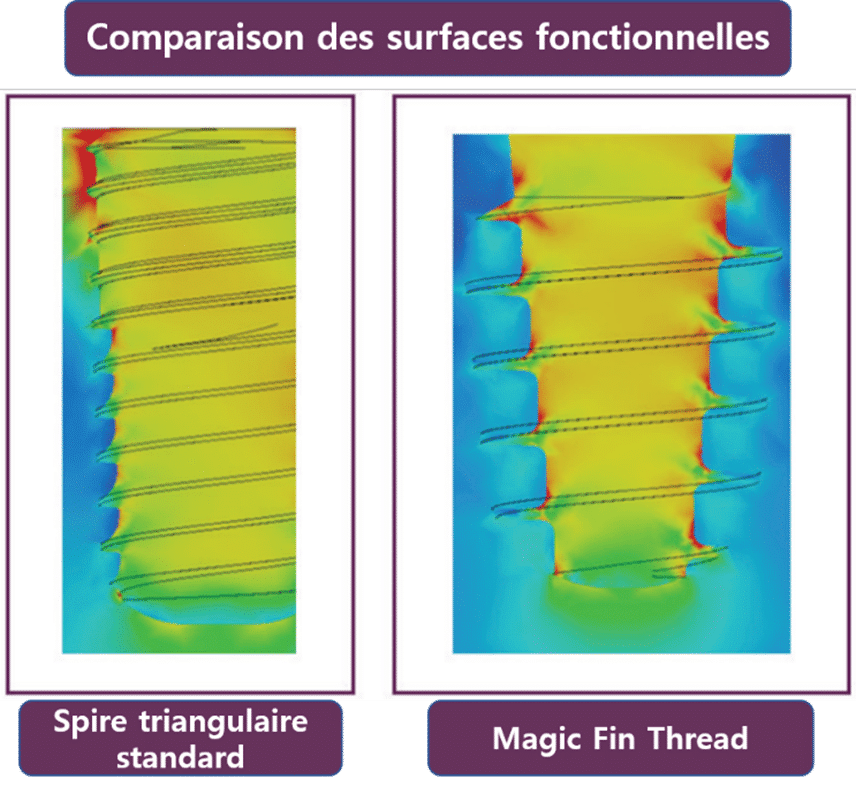

Une autre caractéristique du Magic Fin Thread est sa large surface fonctionnelle. La surface fonctionnelle est étroitement liée à la contrainte mécanique transmise à l’os de la mâchoire, et une surface fonctionnelle plus large peut réduire la perte osseuse autour de l’implant.

Pour évaluer la surface fonctionnelle en fonction de la conception de l’implant, une analyse par éléments finis (FEA) a été réalisée pour comparer le système d’implant bone level en deux parties au niveau de l’os actuellement largement utilisé avec le système d’implant MagiCore (figure 12).

(Figure 12) Comparaison du système d’implant bone level en deux parties et du système MagiCore.

Dans le cas d’une spire triangulaire utilisée pour le pilier et la connexion interne, la force est concentrée à une distance de 5 mm de l’extrémité supérieure. Cependant, avec le Magic Fin Thread, on peut observer que la force est relativement bien répartie, même jusqu’à la région de l’extrémité inférieure du fil. C’est là un avantage unique du MagiCore, qui associe la structure solide du Magic Cuff à une seule ligne de filetage carré, permettant ainsi cette répartition caractéristique des forces.